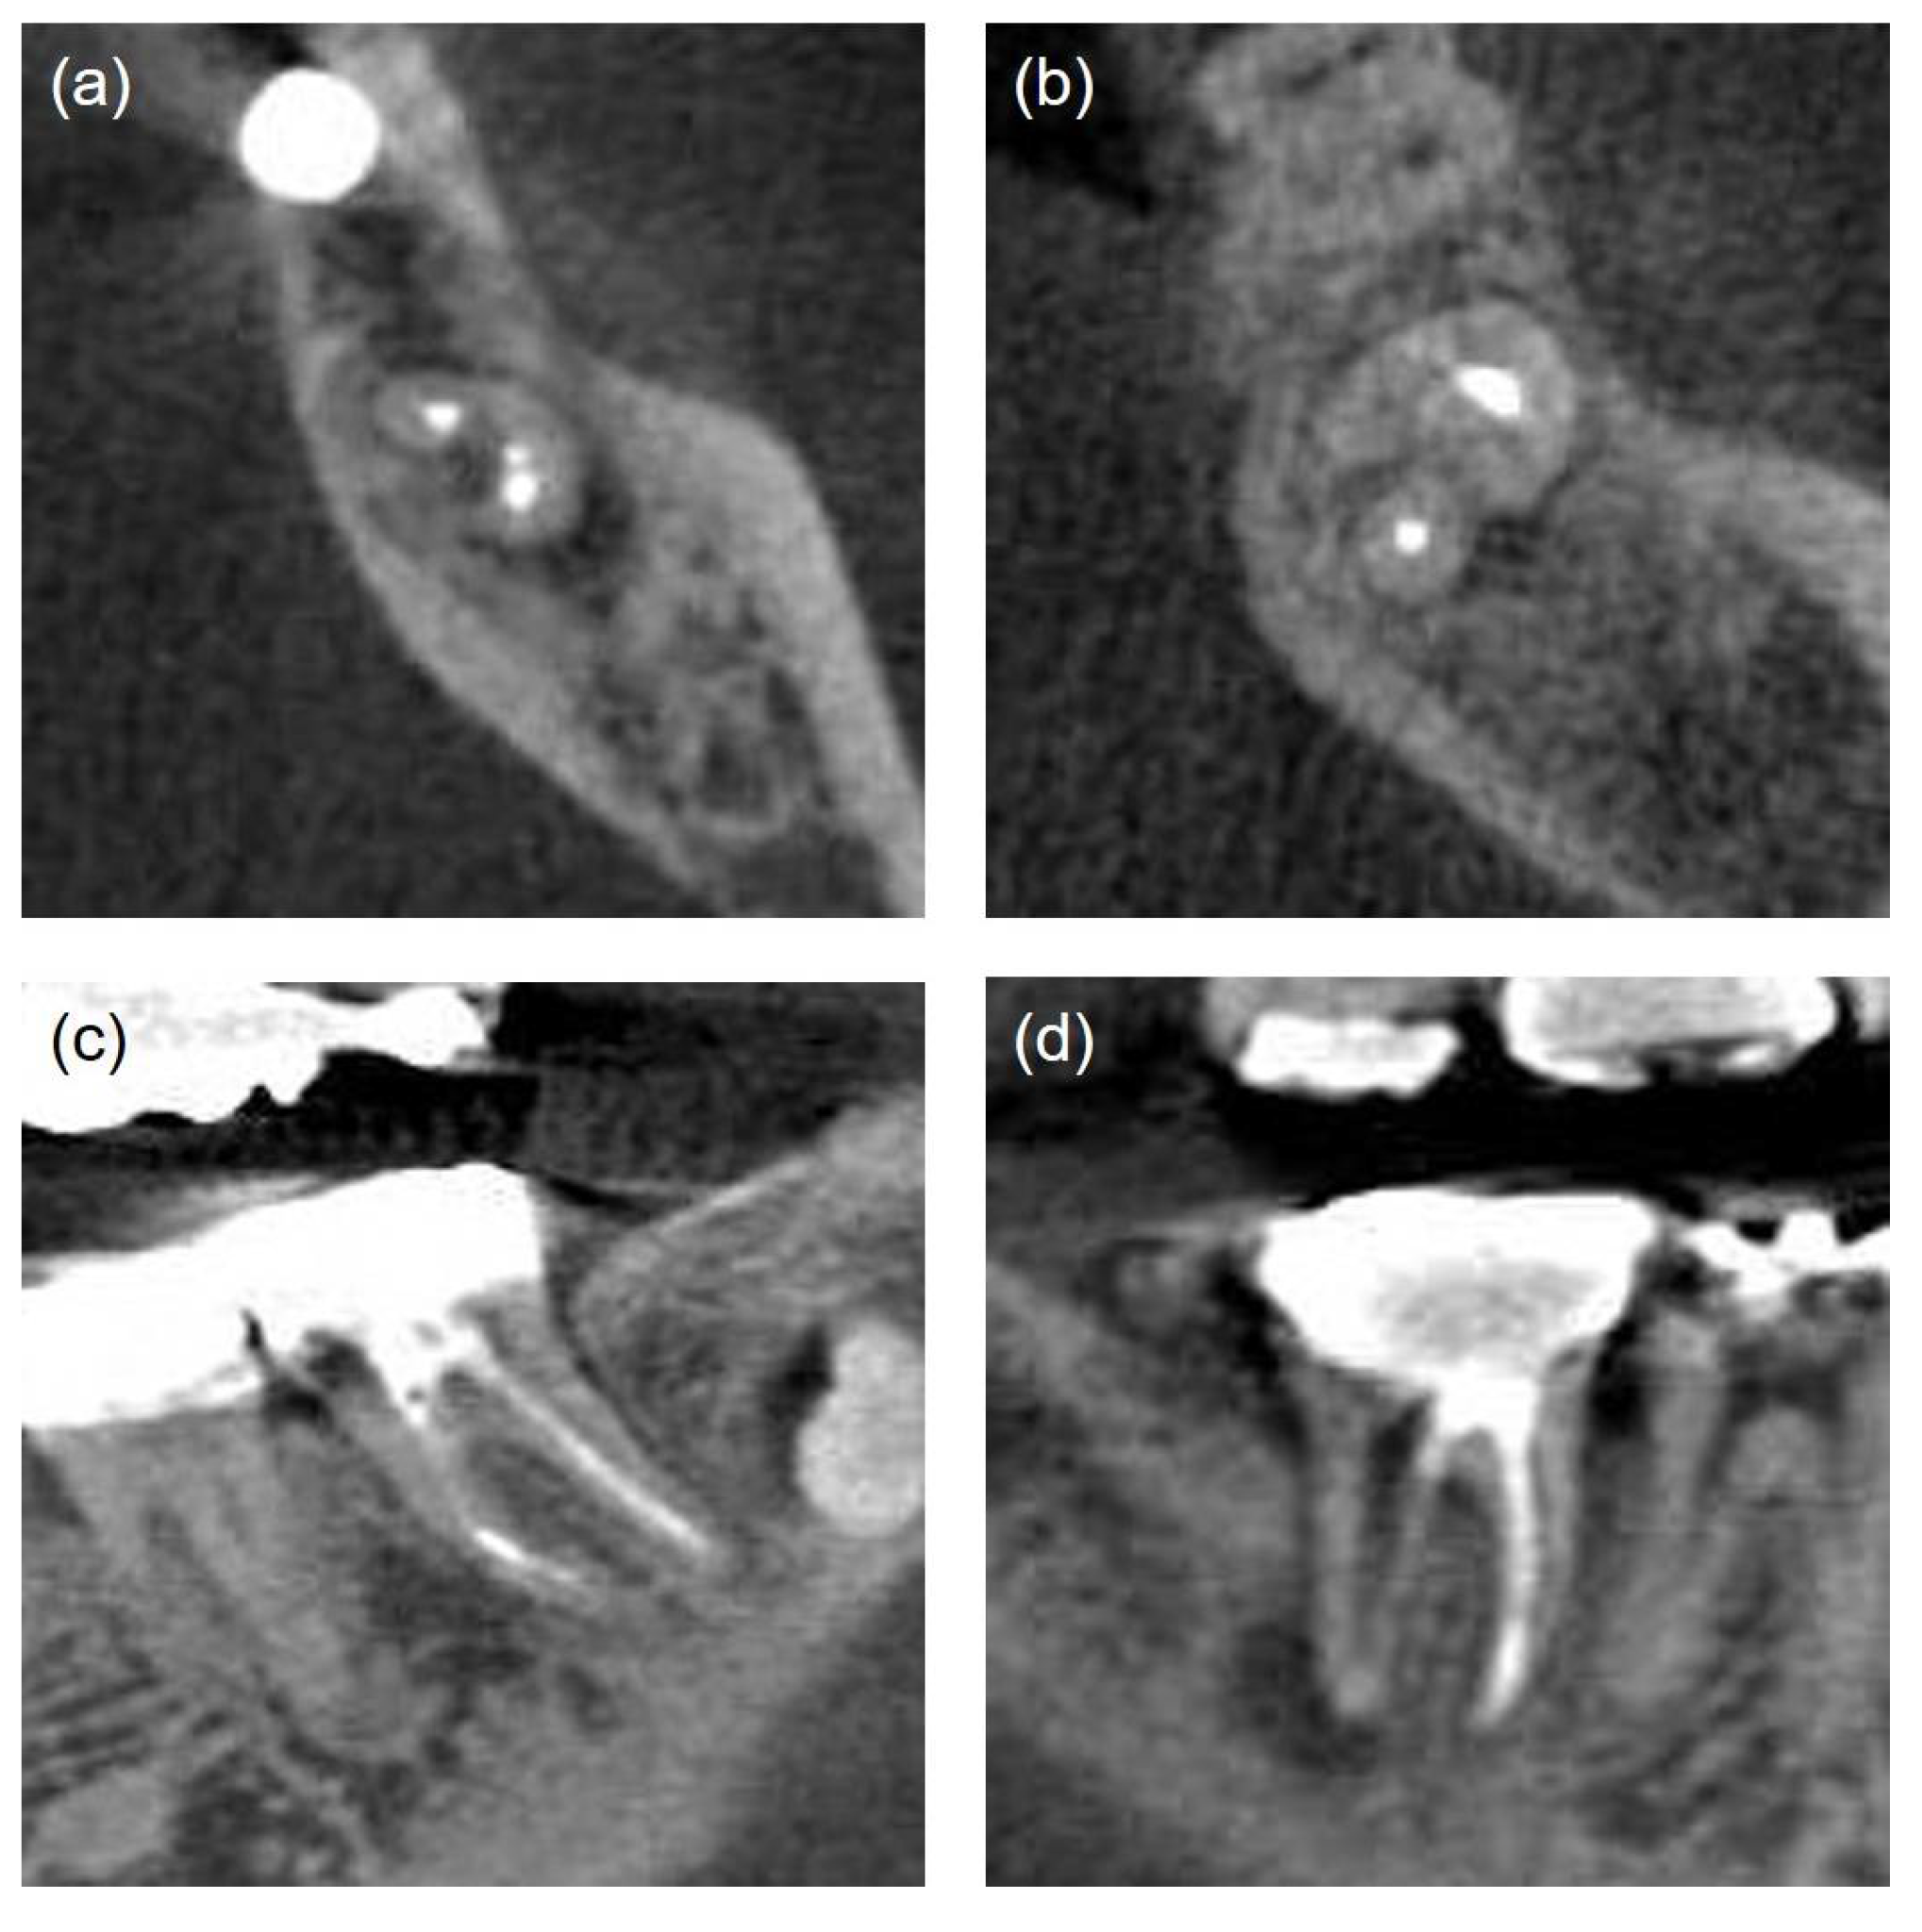

| Obturation density [1] | Good | Homogeneous radiopaque material and no visible space. No more than 2 small voids (<1mm) |

| Poor | Non-uniform radiodensity, with the canal space visible laterally and apically. Isthmus area that had not been treated (Figure 3-a) | |

| Missed canal [17] |

Unfilled canals appearing from cemento-enamel junction to apex including canals splitting from a main canal at coronal, mid, or apical third (Figure 3-b) | |

| Iatrogenic problem | File separation, Perforation (present/absent) (Figure 3-c, d). | |